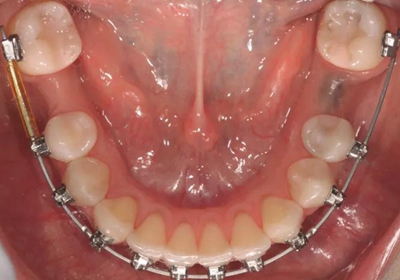

圖4a.病例2在正畸排齊后的臨床和放射學檢查。曲面斷層片顯示,在最初排齊后,雙側(cè)缺失的下頜第一磨牙以及近中傾斜的第二和第三磨牙,計劃在缺牙區(qū)進行種植修復

圖4b.骨增量術(shù)前即刻臨床檢查和PAO 程序顯示,右下第一磨牙部分無牙牙槽嵴的寬度為7mm,左下第一磨牙近遠中距離8mm。同時發(fā)現(xiàn)無牙區(qū)的牙槽嵴明顯吸收

一位31歲的男性患者在15年前拔除了雙側(cè)下頜第一磨牙,現(xiàn)來院要求修復。與上一個病例類似,缺失牙從未修復,導致了牙槽嵴萎縮。接受的治療計劃是正畸種植聯(lián)合治療。右側(cè)上頜第一前磨牙和左側(cè)第二前磨牙因無法修復已經(jīng)被拔除,計劃采用種植體支持的冠來修復。基于患者強烈的愿望,決定保留并維護第三磨牙。臨床檢查和錐束CT檢查顯示雙側(cè)下頜無牙區(qū)骨吸收嚴重,需要在種植位點行骨增量術(shù)并聯(lián)合磨牙直立。

經(jīng)過最初1年的正畸排齊后,右側(cè)下頜第一磨牙無牙區(qū)的近遠中距離由6mm增至7mm,左側(cè)下頜第一磨牙的近遠中距離由7mm增至8mm(圖4)。取得患者知情同意后,采用與病例1中描述的相同技術(shù)和材料進行同期牙槽嵴增量和加速磨牙直立程序(圖5a-5g)。除了右側(cè)磨牙后區(qū),在右側(cè)第二和第三磨牙根部之間也進行了去皮質(zhì)術(shù)(圖5d)。骨增量術(shù)后,即刻將0.016×0.022 英寸帶有30° 后傾彎的鈦鉬合金絲(Dentsply)置于兩側(cè)。6周后,以半個托槽的距離進行主弓絲套推簧雙側(cè)輕加力(圖5h)。